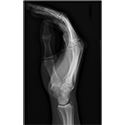

NEUROANATOMY